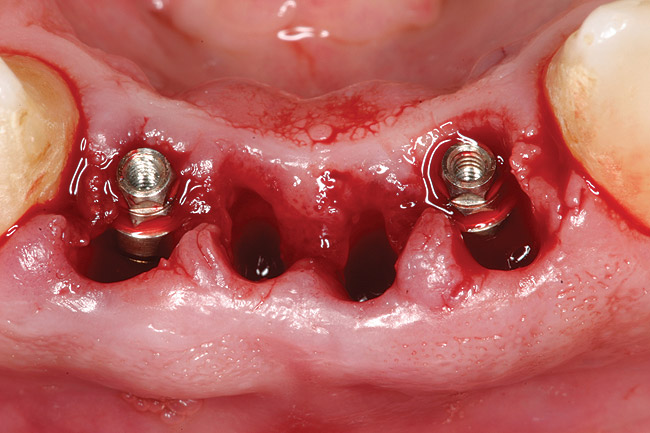

A 53-year-old male presented with localized advanced periodontal disease of the mandibular incisors. Teeth Nos. 23 to 26 exhibited Class II mobility because of advanced bone loss (Figure 1). The teeth had migrated out of position over the years, and a diastema had developed between No. 24 and No. 25 (Figure 2). The patient complained about the poor esthetic appearance of these teeth, and he was able to perceive their loss of strength on function as a result of their mobility.

Preoperatively, 1 g of amoxicillin was administered. Using local anesthesia (lidocaine 1:100,000 epinephrine), extractions of teeth No. 23 to No. 26 were performed without raising a flap and with gentle luxation to preserve the remaining facial osseous plate. The sockets were curetted prior to implant placement. A vacuum-formed surgical guide, fabricated based on a diagnostic wax-up of the desired tooth positions for the subsequent fixed prosthesis, was used during implant placement. Osteotomies were performed at sites No. 23 and No. 26 and positioned toward the lingual aspects of the sockets (Figure 3A and Figure 3B). Two tapered implants (OsseoTite™ 313, BIOMET 3i™, Palm Beach Gardens, FL) measuring 3.25 mm x 13 mm were placed. Conical prosthetic abutments (3-mm height) were used to facilitate joining the two implants in a screw-retained fixed partial denture (Figure 4). A laboratory-processed acrylic-resin provisional restoration was altered to allow connection to the temporary cylinders. The provisional was placed into the vacuum-formed surgical guide that was now used to maintain the provisional in the correct 3-dimensional position (Figure 5) while being attached to the temporary cylinders with acrylic resin intraorally. Once a sufficient amount of acrylic resin was placed to secure the cylinders to the provisional, it was removed from the mouth and its contours were completed at the laboratory bench (Figure 6A). The two central incisor sockets were grafted with small-particle allograft material (Puros® Allograft, Zimmer Dental, Carlsbad, CA) to maintain gingival architecture beneath two ovate pontics (Figure 6B). The provisional restoration was inserted and the screws tightened to 20 Nt-cm of torque.

Figure 1  Preoperative clinical condition.

Figure 1

Figure 4  Tapered implants with conical transgingival abutments and temporary cylinders in place.

Figure 4

Figure 7a  Stage 1 surgery.

Figure 7a